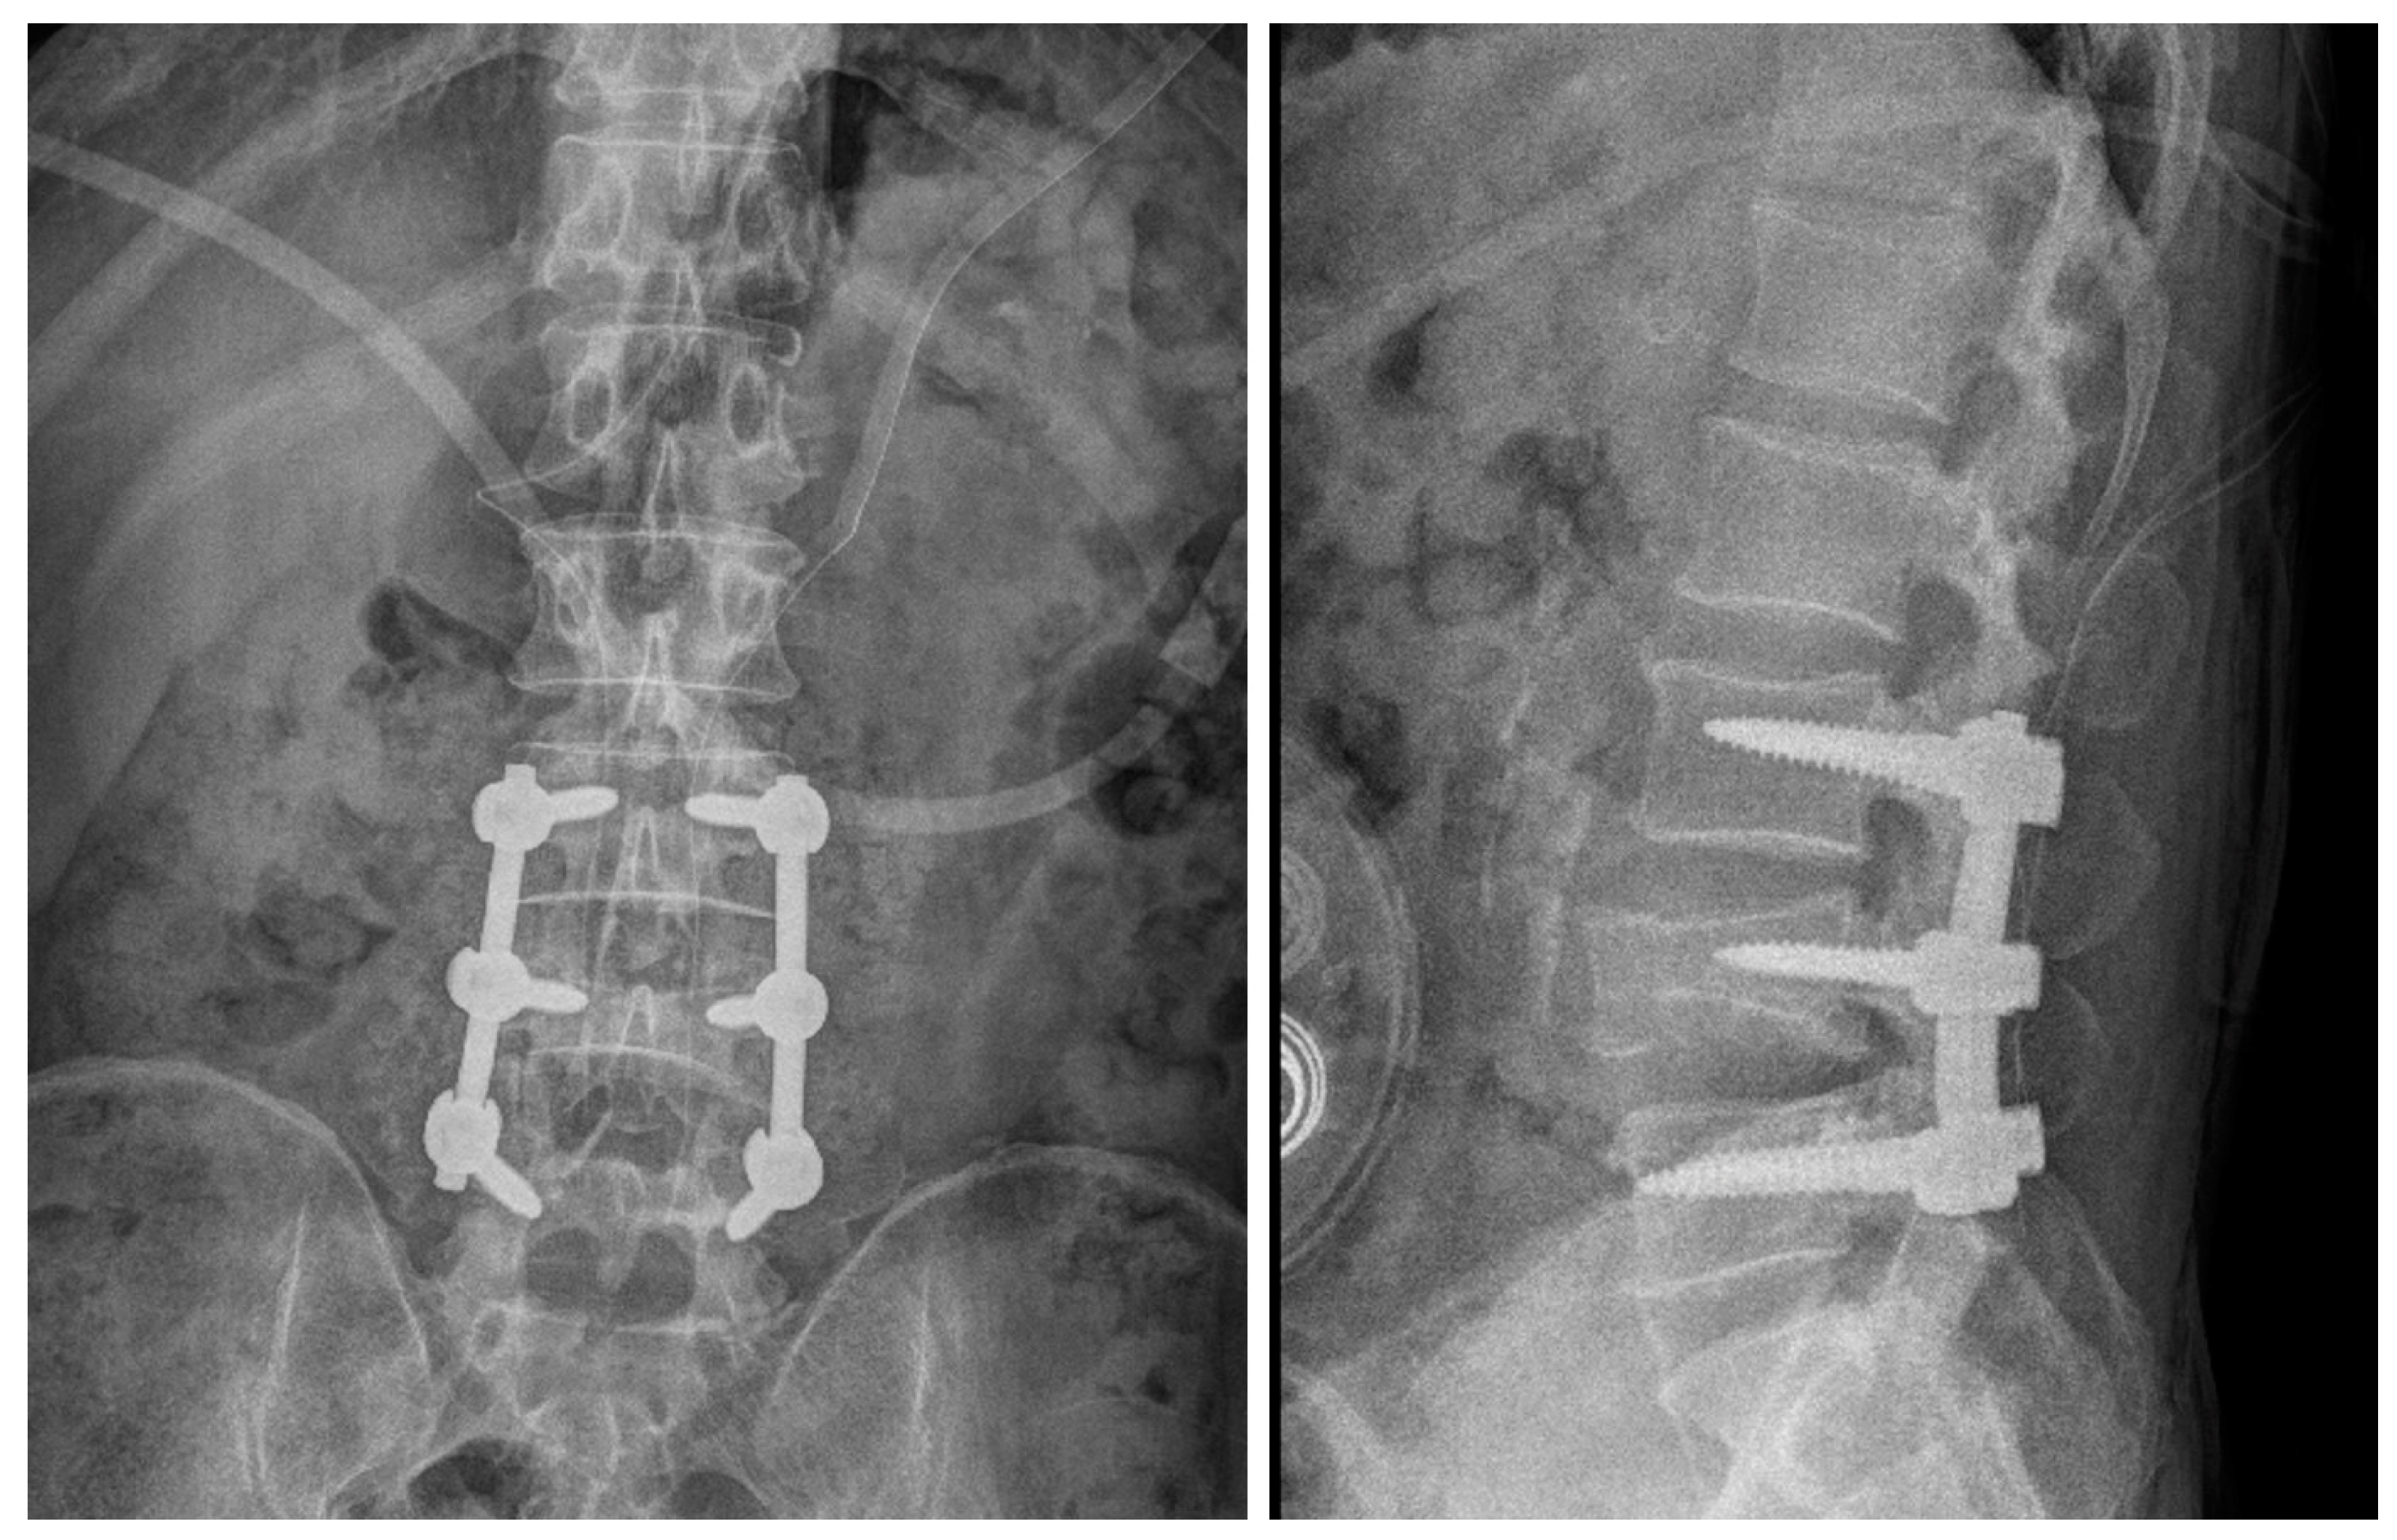

2.1. Case 1

2.2. Case 2